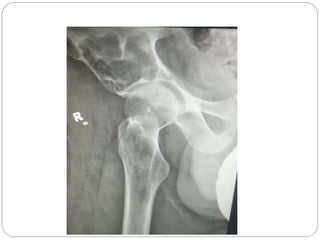

This document discusses 8 oncology cases. Case 1 involves a 40-year old female with right knee pain. Case 2 is a 28-year old male with a left subtrochantric fracture from a MVA who is now experiencing increasing left knee pain and swelling. Biopsy results showed high-grade osteosarcoma. Case 3 is a 30-year old female with breast cancer and bone metastases causing bilateral hip pain.